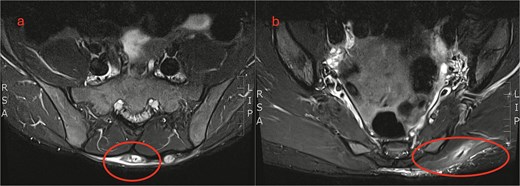

In the general surgery clinic, a 2–3 cm sized swelling over the lumbar region was palpated. Magnetic resonance imaging (MRI) showed a chronic subcutaneous soft tissue mass overlying the sacrum. They also noted a linear extension of similar signal characteristics extending to the left gluteus maximus muscle (Fig. 2).

MRI lumbosacral spine. (a) Axial view shows a soft tissue mass overlying the sacrum. (b) Sagittal view shows a linear extension tracking down to the left gluteus maximus.

The best imaging modalities for organic material is US /MRI [4, 6, 10]. However, MRI is costly, and not readily available so is not recommended for initial assessment [4, 10]. US is easier to access and portable but can be operator dependent [4]. Wood is usually hyperechoic with a surrounding hypoechoic halo from the acoustic shadowing and the inflammatory response [4] (Fig. 3). In this case, the patient had a CT and MRI which demonstrated a soft tissue mass in the lumbosacral region but no foreign body (Figs 1 and 2). With low clinical suspicion, radiologists are less likely to detect a FB or the secondary features of one. In retrospect, the soft tissue mass seen on MRI in the lumbosacral region extending down to the left gluteus maximus corresponds to the sinus tract found intraoperatively. The central T2 hypointense / signal void region represents the wooden splinter which attenuated as it absorbed fluid from the surrounding tissue (Fig. 2).